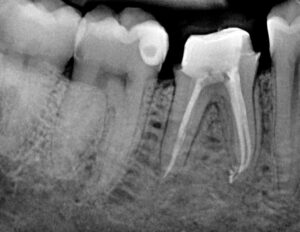

Si parla di trattamento endodontico o di devitalizzazione quando si interviene eliminando la polpa dentaria infiammata e infetta andandola a sostituire dopo un’adeguata disinfezione con materiali da otturazione.

Questa prevede dopo una piccola anestesia locale l’eliminazione di tutto il tessuto dentario affetto dalla carie, l’apertura della camera pulpare e l’eliminazione della polpa dentaria.

Successivamente si procede con la detersione dei canali radicolari e alla loro pulizia tramite strumenti meccanici, in modo da preparare il dente all’otturazione radicolare e alla ricostruzione definitiva.

Nei nostri centri utilizziamo rilevatori apicali per individuare la dimensione precisa delle radici dei denti e sistemi rotanti meccanici per la preparazione dei canali radicolari.